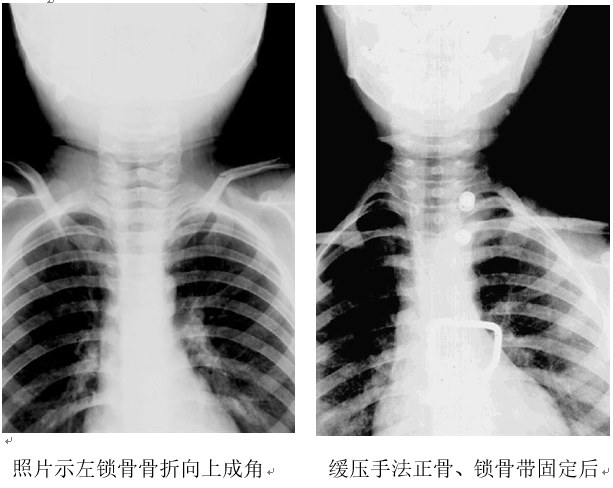

体查:患儿左肩臂拒绝活动,左锁骨中段处向上凸起并有压痛,有轻度纵轴叩击痛。X线照片提示左锁骨中段青枝骨折,对位尚好,向上成角畸形明显。

在骨折断端实施血肿内麻醉后患儿疼痛明显减轻,立即实施缓压复位手法:助手用膝部顶住患儿胸椎后方,轻轻向外、后方牵拉双肩部,术者用大拇指叠加缓缓向下按压锁骨骨折成角处,并且边按压边与患儿交谈,以缓解紧张情绪。经过数分钟的按压后,骨折成角畸形消失,随即在锁骨中段上方垫好压垫,绑上锁骨固定带。即刻照片见锁骨骨折成角畸形完全纠正,达到了解剖对位。